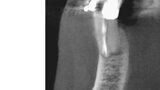

3D technologie v diagnostice a léčbě endodontických onemocnění